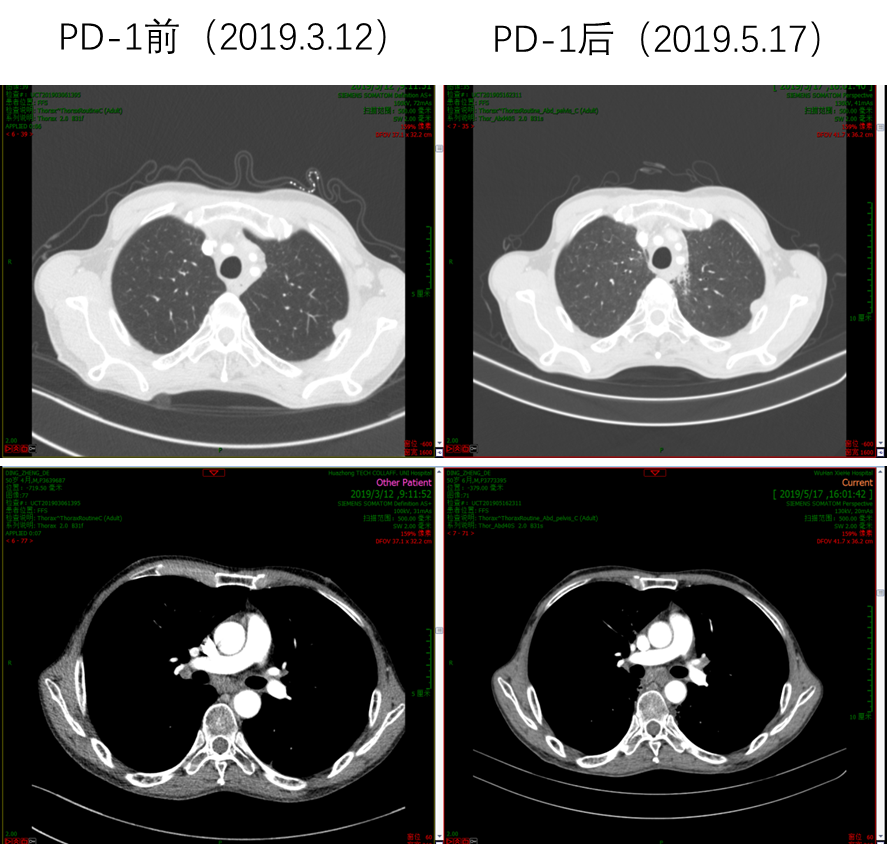

因患者PS评分差,故推荐单药PD-1单抗治疗,患者考虑后选择信迪利单抗。2019年3月20日开始使用信迪利单抗治疗1次,当日出现发热39.3℃,予以退热栓退热治疗后好转。4天后,患者PS评分明显好转,下床活动自如,食欲增强,PS评分由3分改善到1分。2019年4月11日和2019年5月1日分别再使用信迪利单抗治疗各1次。2019年5月17日复查腹部CT,肝脏病灶较前明显缩小,肝门淋巴结较前明显缩小;复查胸部CT,肺部病灶也较前明显缩小。总体疗效评价为PR。多次治疗中外周血EBV-DNA拷贝数检测结果显示,信迪利单抗治疗后EBV-DNA明显降低。

image021.png

图6  信迪利单抗治疗前后肺部病灶明显缩小